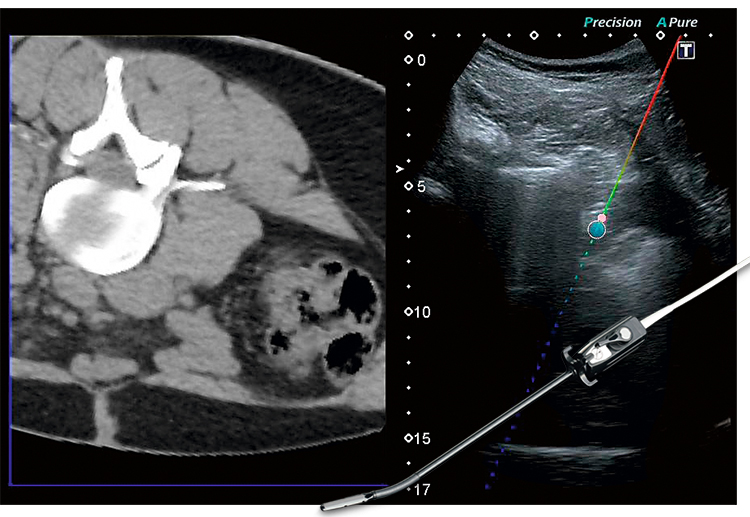

Совмещает изображение полученные на КТ и МРТ, с изображением, получаемом в процессе УЗ-диагностики.

Функция Smart Navigation системы Aplio позволяет улучшить точность и повысить безопасность пациента во время проведения абляционных процедур.

Лапароскопический датчик позволяет проводить малоинвазивные процедуры, выполнение биопсий, а также абляции под ультразвуковым контролем.